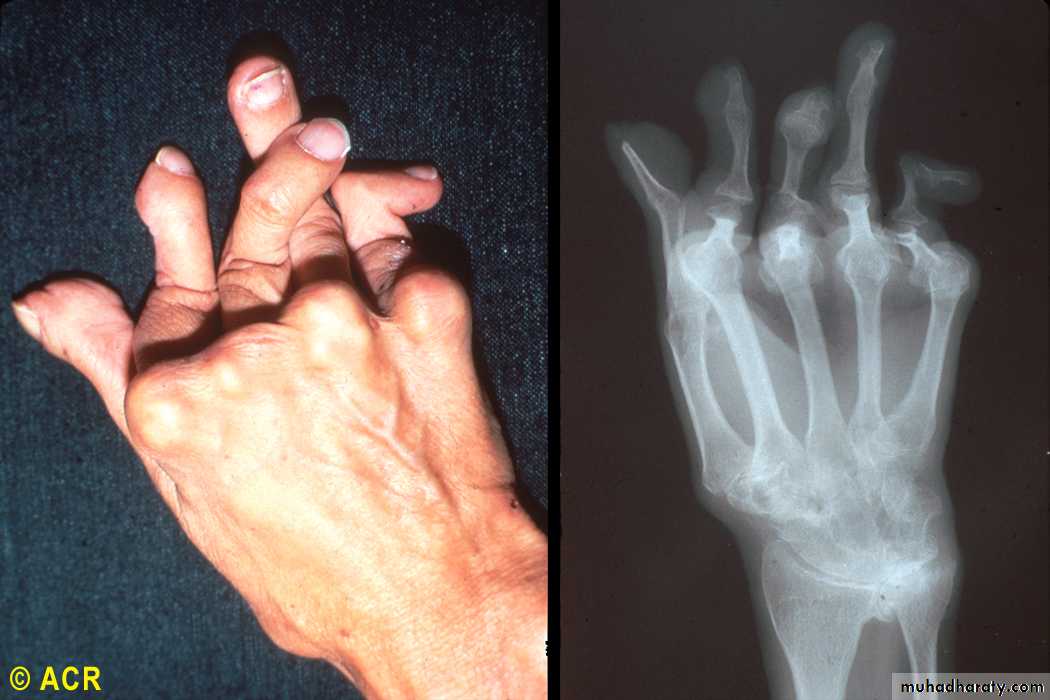

Rheumatoid arthritis: arthritis mutilans, hand (clinical and radiograph)

24

the most helpful laboratory procedure. The fluid is inflammatory, with more than 10,000 white blood cells and a predominance of polymorphonuclear leukocytes, typically 80% or more. Rheumatoid factor, an IgM antibody directed to IgG, is found in 80 to 90% of patients with RA.... XR-Findings

Peri articular osteopeniaMarginal erosions (at least months of persistent activity)

Joint space narrowing (cartilage loss)

Ankylosis (wrists)

Deformities